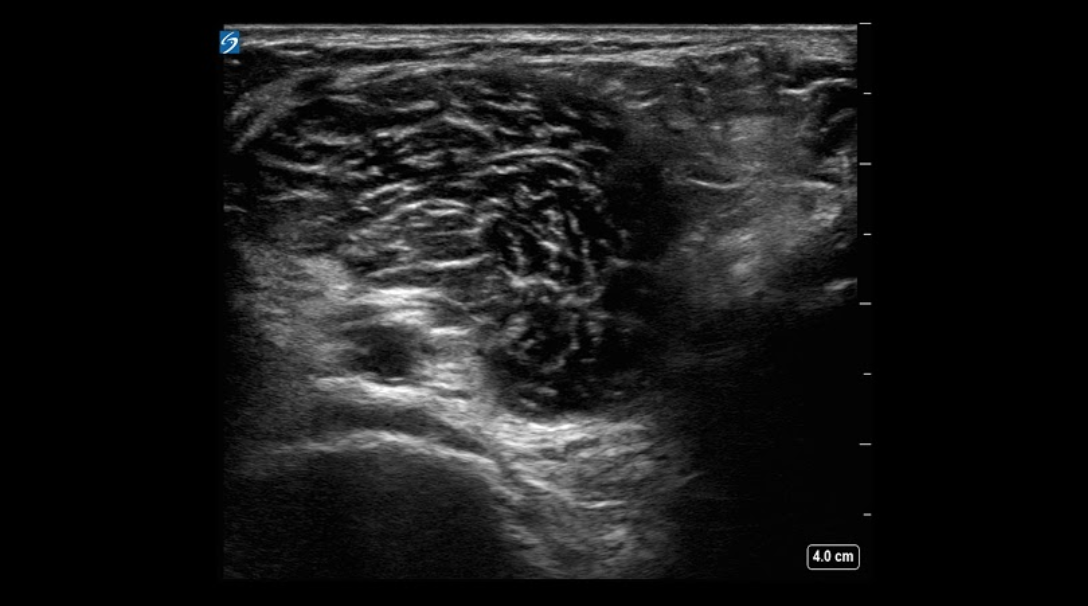

Knee Neurovascular Structures Image